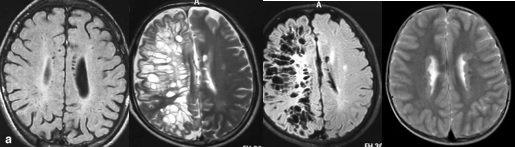

重要申明:以下每个部分会配磁共振图片,因疾病和影像之间存在同病异象、同像异病,为避免误导,图片不标注疾病,请各自鉴赏,另其中有部分图片来源于网络,有疑问可与本人联系。

代谢性脑病的原因很多,包括氨基酸、有机酸、脂肪酸、糖等代谢异常,以及线粒体功能障碍等,导致高氨血症、低血糖、酸中毒和能量缺乏,引起脑功能障碍。我们在临床上看到的有缺血缺氧性脑病、低血糖致白质脑病、肝性脑病、肾性脑病、Wernicke脑病、线粒体脑病等。中枢神经系统受累的病灶在磁共振上可出现各种表现。

脱髓鞘,多发性硬化(MS)、视神经脊髓炎(NMO)、急性播散性脑脊髓炎(ADEM)、MOG相关性脱髓鞘病变、自身免疫性脑炎、CNS血管炎、神经系统结节病、Susac's Syndrome、Clippers’综合症、桥本氏脑病等。还有如急性、亚急性的放疗损伤等。